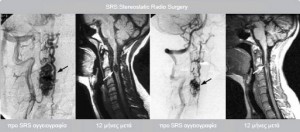

Η επιτυχία που παρατηρείται στην ακτινοχειρουργική αντιμετώπιση των αγγειακών δυσπλασιών του εγκεφάλου προβλέπεται να επαναληφθεί στην σπονδυλική στήλη και άλλα σημεία του σώματος.

Το κέντρο μας διαθέτει μεγάλη εμπειρία στην αντιμετώπιση αγγειακών δυσπλασιών και σηραγγωδών αιμαγγειωμάτων.

Έχουμε αντιμετώπιση περισσότερο από 131 ασθενείς με AVM, με ποσοστό εξάλειψης >90% στη διετία. Αναμένεται από τη θεραπεία μείωση του όγκου του AVM κατά 50% με το μέγιστο να καταγράφεται στην τριετία όποτε και αν υπάρχει υπολειπόμενος ιστός και εφόσον κριθεί απαραίτητο να χορηγείται με ασφάλεια συμπληρωματική δόση.